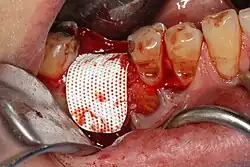

Socket preservation attempts to prevent bone loss by bone grafting the socket immediately after extraction. With the procedure, the gum is retracted, the tooth is removed, material (usually a bone substitute) is placed in the tooth socket, it is covered with a barrier membrane, and sutured closed.[2] Roughly 30 days after socket preservation, the barrier membrane is either removed, or it resorbs, and the callous of bone covers with new gingiva. While there is good evidence that socket preservation prevents bone loss, there is no definitive proof that this leads to higher implants success or long-term health.[4]

Socket preservation is completed at the time of extraction. After removal of the tooth, the gum is elevated away from the bone, the socket is thoroughly cleansed, and antibiotic powder may be used. A barrier membrane is then fastened to the gum, the socket is packed with bone grafting material and the wound closed over the barrier membrane. Where the barrier membrane does not dissolve, it is removed approximately 30 days after placement,[5] and the graft becomes incorporated into the healing bone 3–9 months later.

Barrier membranes can be either resorbable, or non-resorbable. The standard non-resorbable membrane is expanded polytetrafluoroethylene (ePTFE) which was first used in 1984, when it was found to be biocompatible. There are a variety of resorbable membranes, including collagen,[7] and synthetic resorbable (lactic acid or glycolic acid).